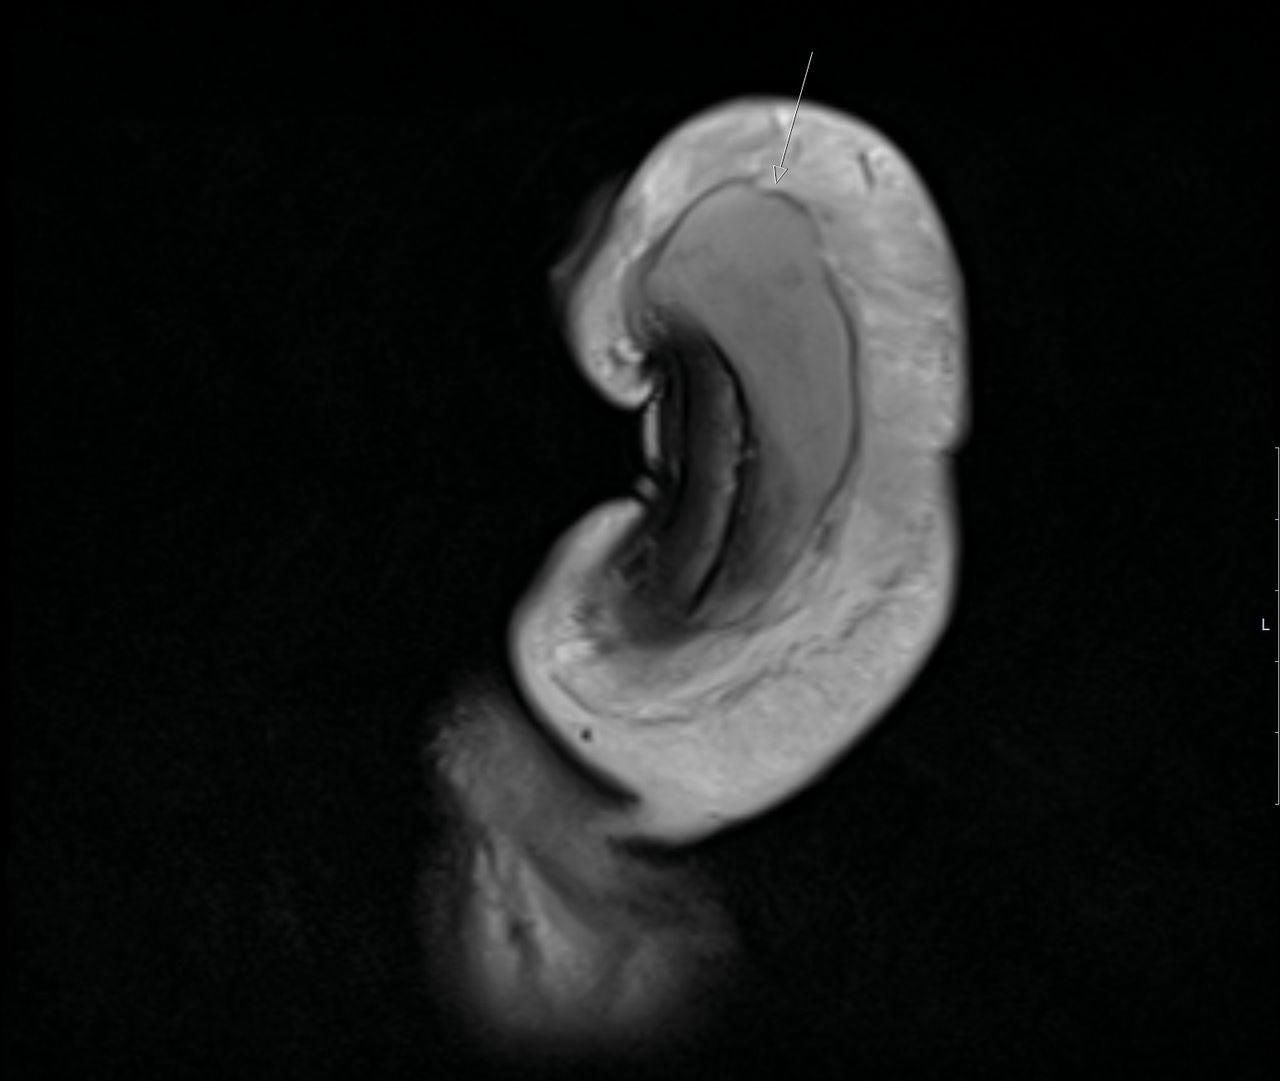

The surgeon confirmed, however, that “indeed there was a 3cm vertical tear” in his snapped penis. This requires surgical intervention within 24-hours to reduce the risk of long-term complications such as “erectile dysfunction, excessive penile curvature or urethral stenosis.”